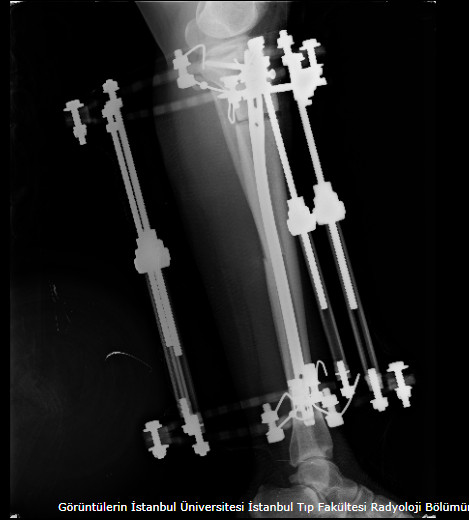

Lengthening SurgeryDec 30, 2021 | Case Examples Case 1: Tibiada Extension Over Nail (LON) Case 2: Femurda Extension Over Nail (LON Case 3: Femurda Automatic Nail Extension